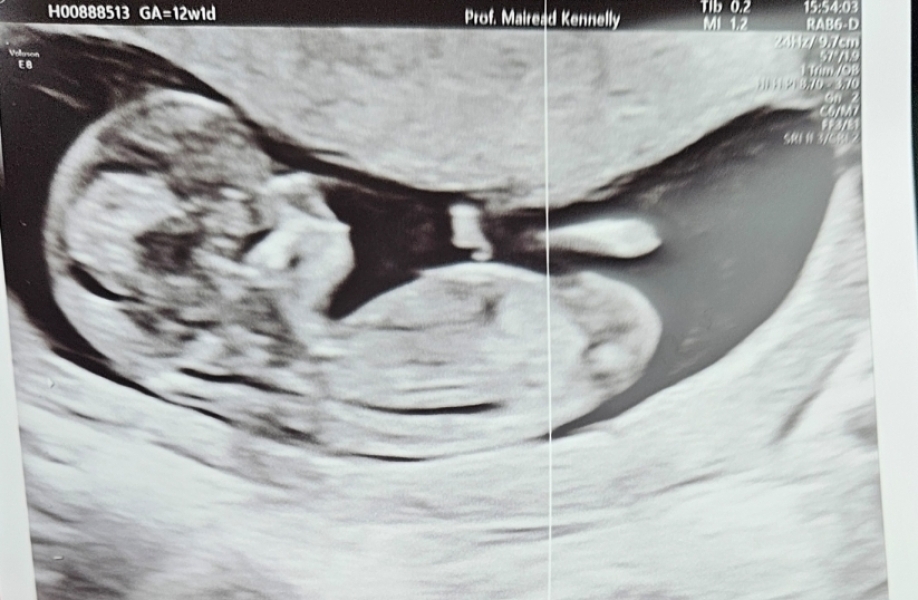

Sorry I'm only writing in now, girls. I was just so tired last night 😂 all was perfect at the 12 week scan. Strong heartbeat, measuring exact and a very active baby. The relief! I feel I can relax a bit now, especially with the NIPT results as well yesterday.

At least we avoided Christmas babies!

@SureLook that's a lovely picture, and great news. Do your best to relax and enjoy it now if you can!

Ah thats such a fantastic picture!! I know its easier said than done when people say to relax and enjoy it!